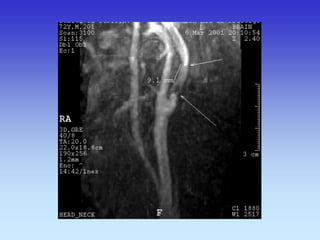

METODE PRIKAZA KRVNIH ŽILA

•UZ-DOPPLER

•DSA

•CTA

•MRA

B-mod i obojeni Doppler karotidne arterije

VASKULARNA OPSKRBA WILLIS-ijev prsten

a. cerebri ant.

a. cerebri media

a. cerebri post.

VASKULARNA OPSKRBNA PODRUČJA